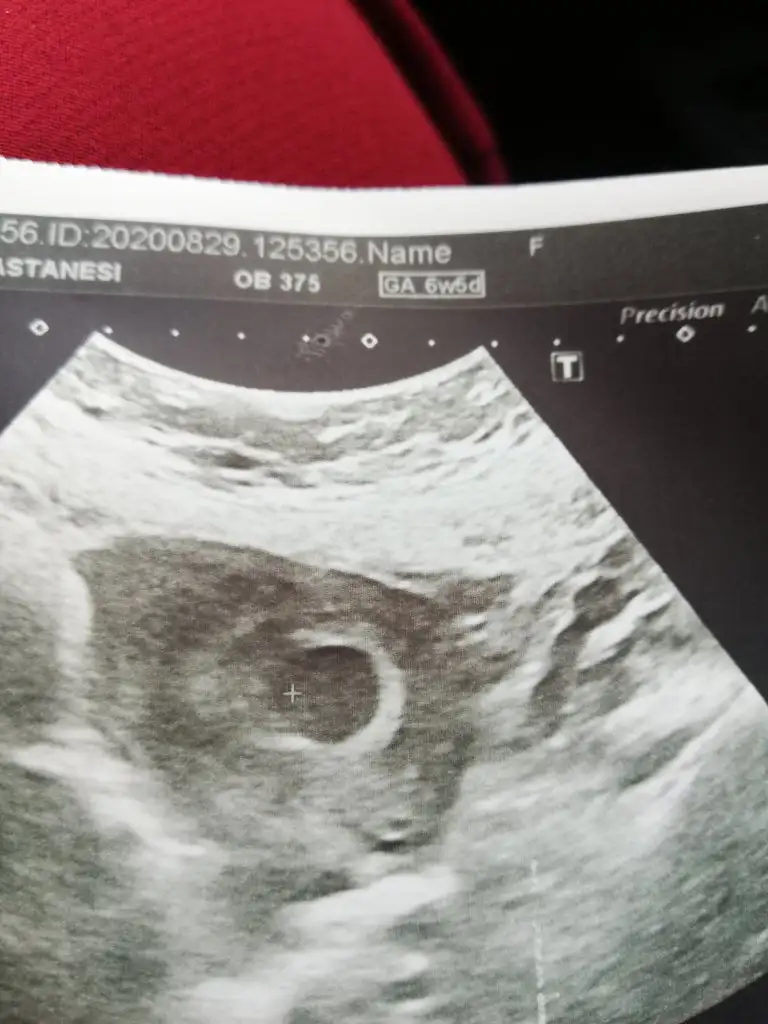

Bana da bi tahminde bulunur musun canım? Bugünün ultrasonu.

Sanki kız gibi 13 hafta olursa paylasinMerhabaIkra meyra cinsiyet tahminini sabırsızlıkla bekliyoruz arkadaşımın usg’si